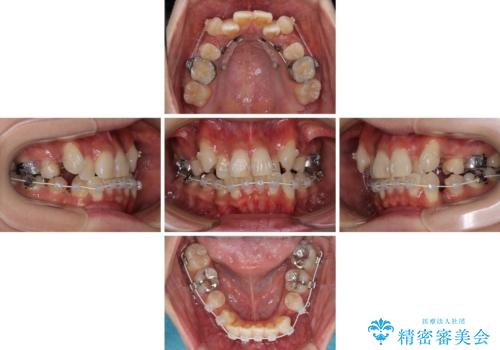

- ハーフリンガル

目立たない装置を希望されたので、上顎が裏側装置のハーフリンガルを選択し、上下左右の小臼歯(計4歯)を抜歯して矯正治療を行うこととしました。

補助装置を併用することで、八重歯を速やかに改善し、治療期間の短縮を図ることとしました。